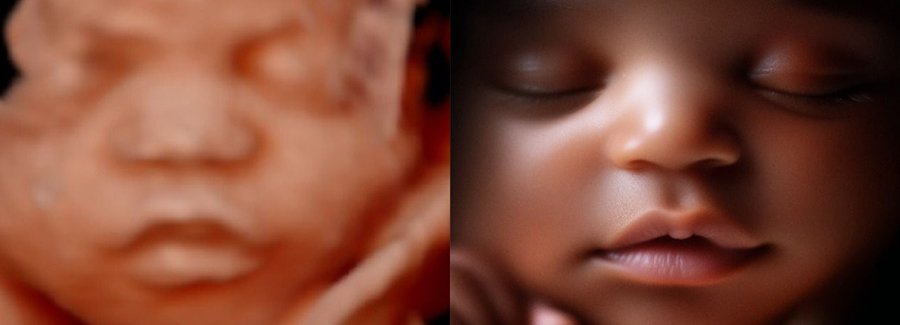

Often referred to as 5D, HD or FRV (fetal realistic view), 5D/HD is the newest development in pregnancy imaging. It captures and combines high definition volume data to create automated images with amazing color and clarity so you can see your baby as though you were looking from inside the womb.